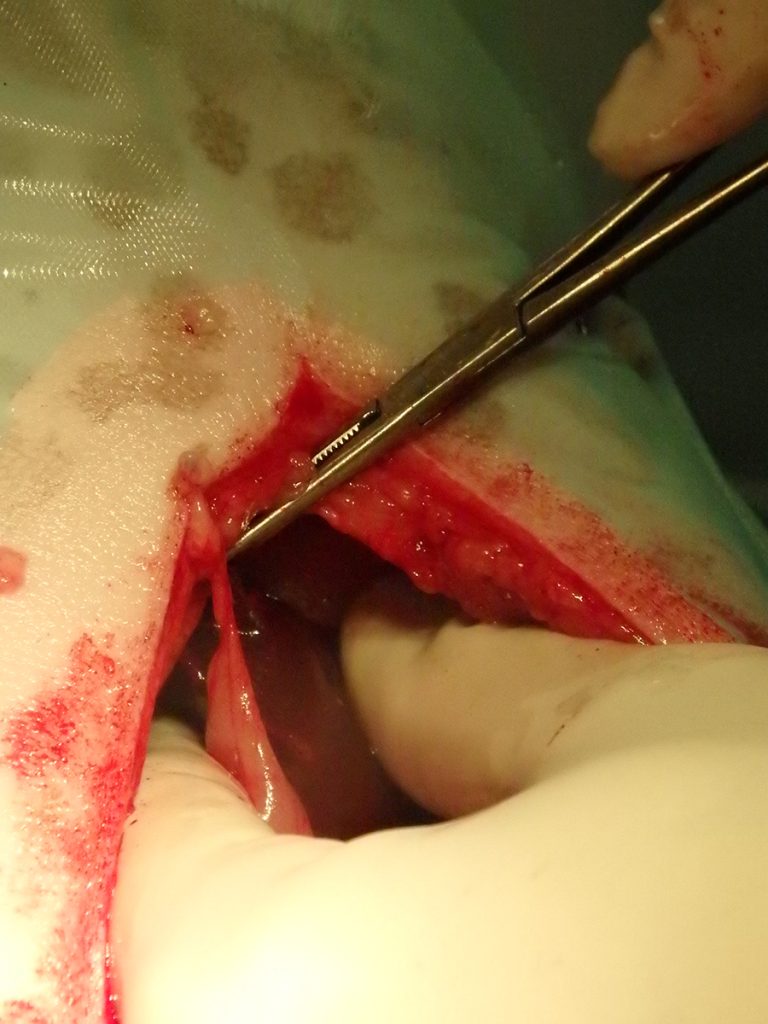

Na het openen van de buik en het verwijderen van wat vet, is de chirurg gaan zoeken. Al snel vindt hij aan de voorzijde van de maag een vreemd vliesje. Dit blijkt een stukje vet en vlies te zijn, wat op het oogje van de naald verkleefd zat. Ruim 2/3 van de naald blijkt in een leverlob te zitten. De naald blijkt er niet eenvoudig uitgetrokken te kunnen worden. Hij zit aardig vast. Dit suggereert dat hij er misschien al iets langer zit. Bij het verwijderen van de naald ontstaat er een klein scheurtje in de lever. De bloeding kan worden gestelpt met een speciaal matje dat stolling bevordert. Hierna is het een kwestie van de buik sluiten en Lady mag weer wakker worden.